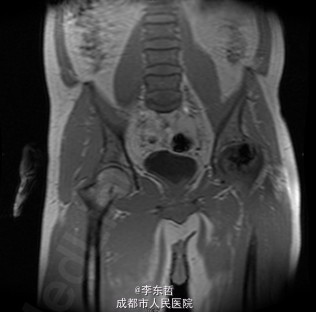

患者男,31岁,因“左股骨头股骨颈骨折切开复位内固定术后1+年”入院。患者1+年前因车祸致左股骨头、颈粉碎性骨折伴坐骨神经损伤于我院就诊,于我院行左股骨头股骨颈骨折切开复位空心钉+可吸收镙钉内固定术,术后恢复良好出院。术后8月后扶双拐活动。7月前患者无明显诱因出现左髋部疼痛,以负重时为重,后患者只能扶双拐活动。现患者为进一步治疗入我院。患病以来患者精神可,食欲可,睡眠可,大小便未见明显异常,体重无明显变化。

查体:T:36.2oC,P:80次/分,R:20次/分,BP:112/74mmHg。神志清楚,无病容,皮肤巩膜无黄染,全身浅表淋巴结未见肿大。颈静脉搏动、心界正常,心律齐,各瓣膜区未闻及杂音。胸廓未见异常,双肺叩诊呈清音,双肺呼吸音清,未闻及干湿啰音及胸膜摩擦音。腹部外形正常,全腹柔软,无压痛及反跳痛,腹部未触及包块,肝脏肋下未触及,脾脏肋下未触及,双肾未触及。双下肢无水肿。视:左髋外侧可见一约30cm手术瘢痕,其上可见一点状结痂,左腿较右腿短缩,左腿肌肉较右腿萎缩,步态异常。触:左髋部无压痛,左腿外侧感觉异常,以左膝外侧为重,左髋外侧叩击痛,左足背动脉搏动未扪及异常。动量:左下肢较右下肢短缩约3cm,左髋关节活动受限,其余各关节未见明显异常。

入院诊断:左股骨头股骨颈粉碎性骨折切开复位内固定术后坏死;积极完善术前检查及准备后行关节置换术。